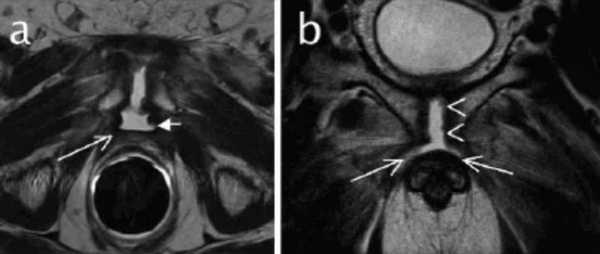

МРТ-признаки остеомиелита лонных костей: расширение сочленения и скопление жидкости с формированием параартикулярных затеков (длинные стрелки), разрастание грануляционной ткани (короткие стрелки), Т2-ВИ, аксиальная (а) и коронарная (в) плоскости

Заболевания костей малого таза

Магнитно-резонансное сканирование нашло применение в травматологической, ортопедической, ревматологической, онкологической практиках, так как генез патологических процессов многообразен. Исследования проводят для диагностики причин острой и хронической боли.